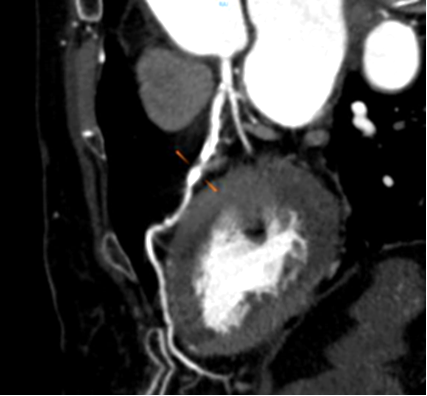

Công nghệ tim mạch Aheart

Khám phá nhiều hơn, đi sâu vào từng chi tiết

Công nghệ DE tiên tiến: Tích hợp đa dạng kỹ thuật năng lượng kép, hình ảnh rõ nét

Phân tích toàn diện: Cung cấp đồng thời đánh giá định tính và định lượng chuyên sâu.

Giá trị lâm sàng vượt trội: Hỗ trợ nâng cao độ tin cậy trong chẩn đoán và điều trị.

Hình ảnh lâm sàng